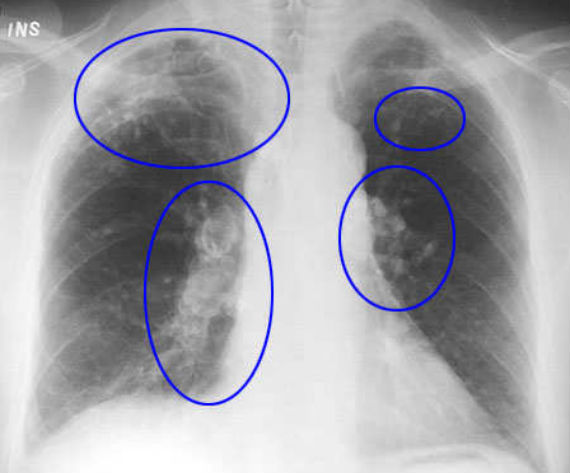

Los Centros para el Control y la Prevención de Enfermedades de Estados Unidos llama a los gránulos finos liberados por la extracción de arena "sílice cristalizado respirable", o polvo de sílice, el cual, asegura, está vinculado a la silicosis y el cáncer de pulmón.

Las muertes y enfermedades que ocurren entre los trabajadores que limpian con chorros de arena o que perforan rocas son indicadoras de la gravedad de los riesgos de salud asociados con la exposición a la sílice. El hecho de respirar el polvo de sílice cristalina puede causar silicosis, que en sus aspectos más severos puede resultar en la discapacidad o la muerte. El polvo de sílice respirable entra en los pulmones y crea la formación de tejido de cicatriz reduciendo la capacidad de absorción de oxígeno por los pulmones. La silicosis no tiene cura. Dado que afecta el funcionamiento de los pulmones, uno es más susceptible de contraer infecciones pulmonares como la tuberculosis.